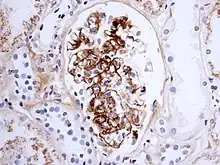

Immunostaining showing IgA in the glomerulus of a patient with Henoch-Schönlein nephritis.

The disease derives its name from deposits of immunoglobulin A (IgA) in a granular pattern in the mesangium (by immunofluorescence), a region of the renal glomerulus. The mesangium by light microscopy may be hypercellular and show increased deposition of extracellular matrix proteins. In terms of the renal manifestation of Henoch–Schönlein purpura, it has been found that although it shares the same histological spectrum as IgA nephropathy, a greater frequency of severe lesions such as glomerular necrosis and crescents were observed. Correspondingly, HSP nephritis has a higher frequency of glomerular staining for fibrin compared with IgAN, but with an otherwise similar immunofluorescence profile.[4]